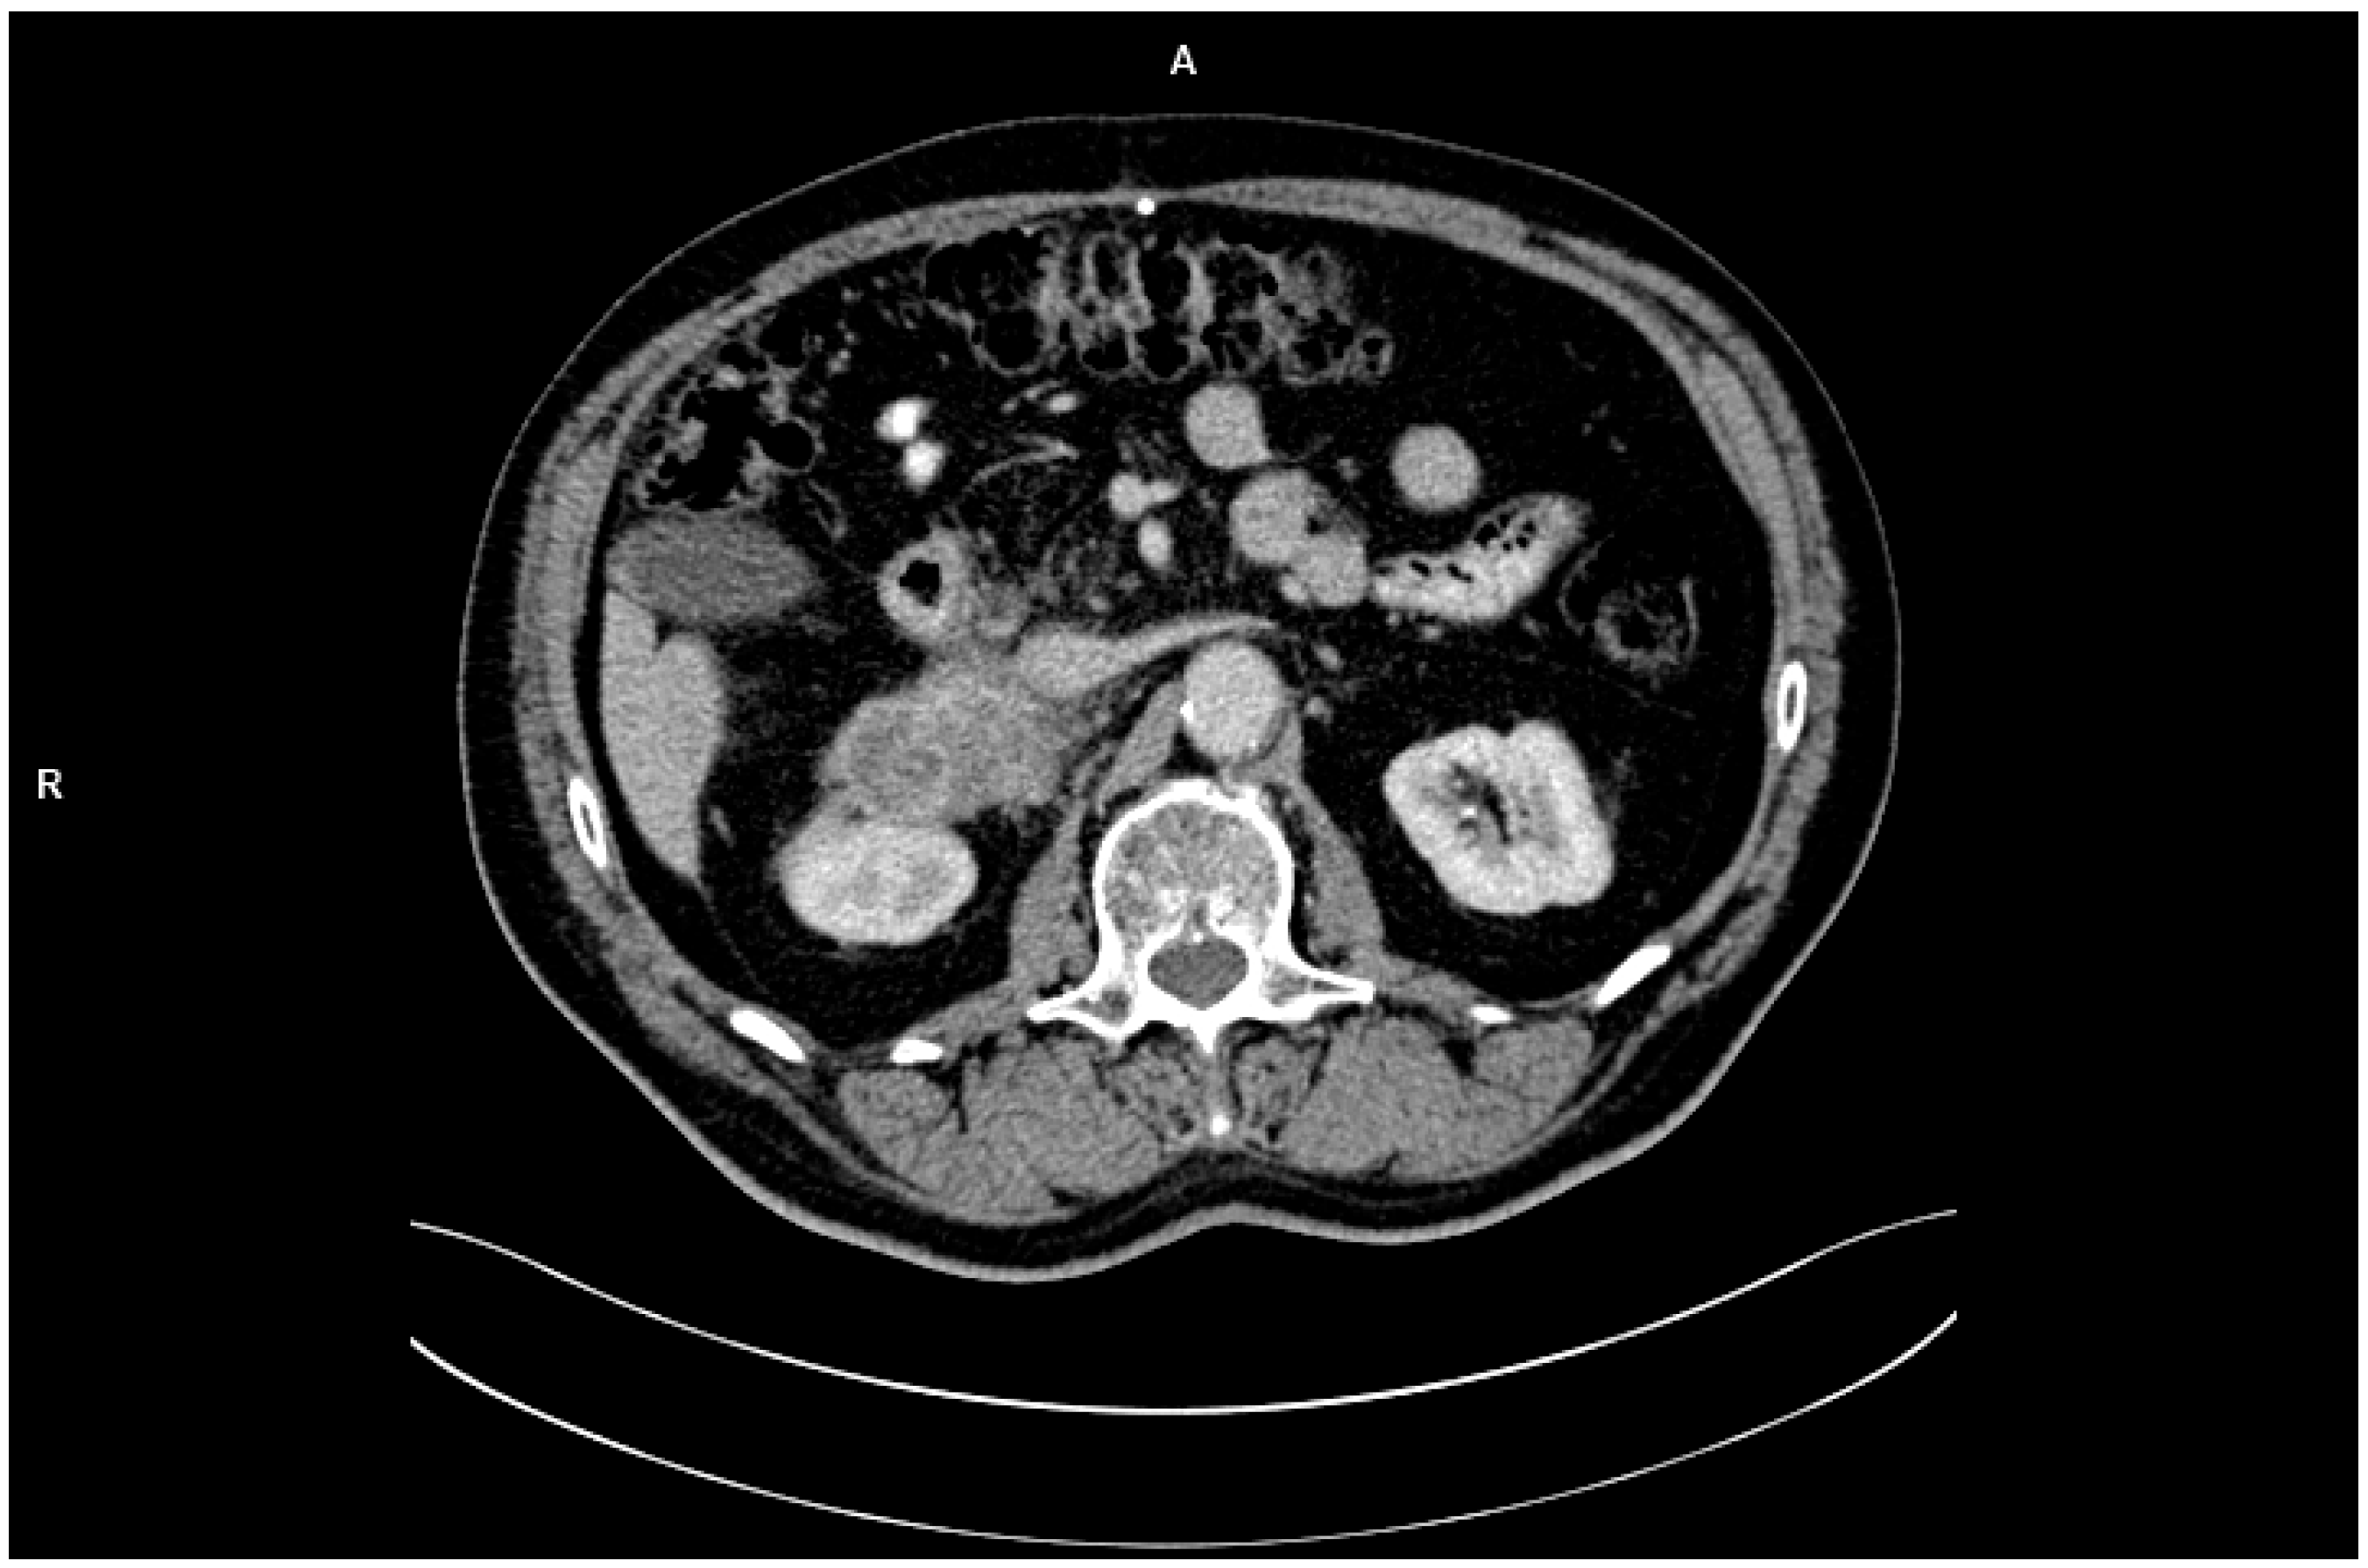

In February 2023, the patient independently underwent abdominal CT imaging, which identified a 7 × 9 cm mass in the right adrenal gland, raising suspicion of metastatic disease (Figure 1). Subsequent PET-CT imaging confirmed the presence of a metabolically active tumor with high glucose uptake and additional lymphadenopathy in the retroperitoneal space. Biochemical analyses demonstrated that the adrenal tumor was hormonally inactive.

PET-CT showed intense [18F]FDG uptake in the adrenal tumor area, with a maximum SUVmax = 12.8. The elevated metabolic activity of the lesion was consistent with the tumor phenotype, while the lack of significant uptake in other organs suggested limited disease progression at the stage of detection. SUV values in adrenal adenomas typically do not exceed 3.5, which further supported the diagnosis of a metastatic lesion. The CT image showed an irregularly limited lesion measuring 7 × 9 cm, infiltrating adjacent structures. In the clinical context, these imaging features indicated the advanced nature of the metastasis and its unresectability.

Figure 1. CT imaging with identified a 7 × 9 cm mass in the right adrenal gland.